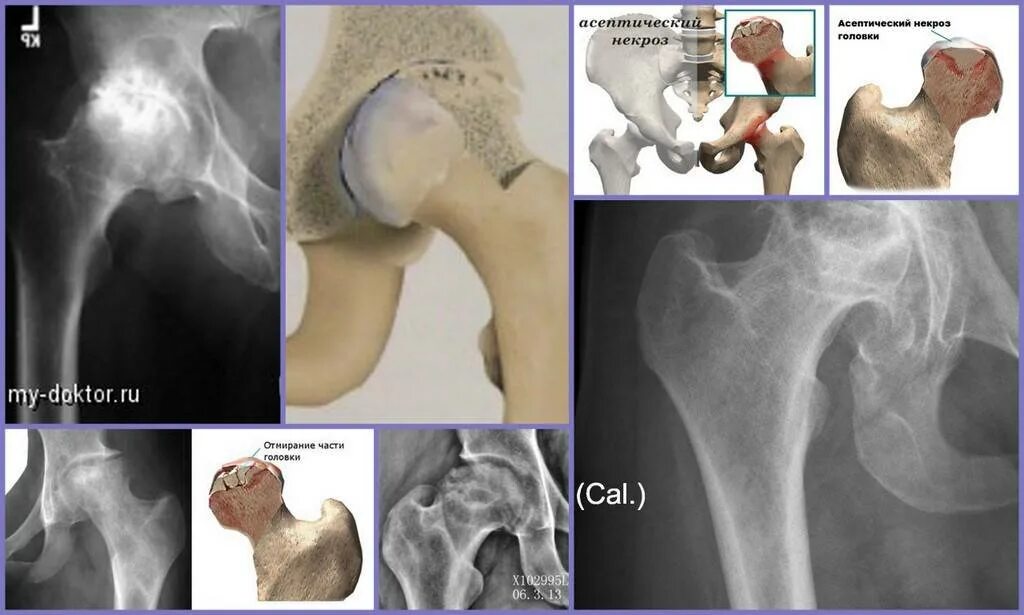

Некроз головки тазобедренного сустава лечение